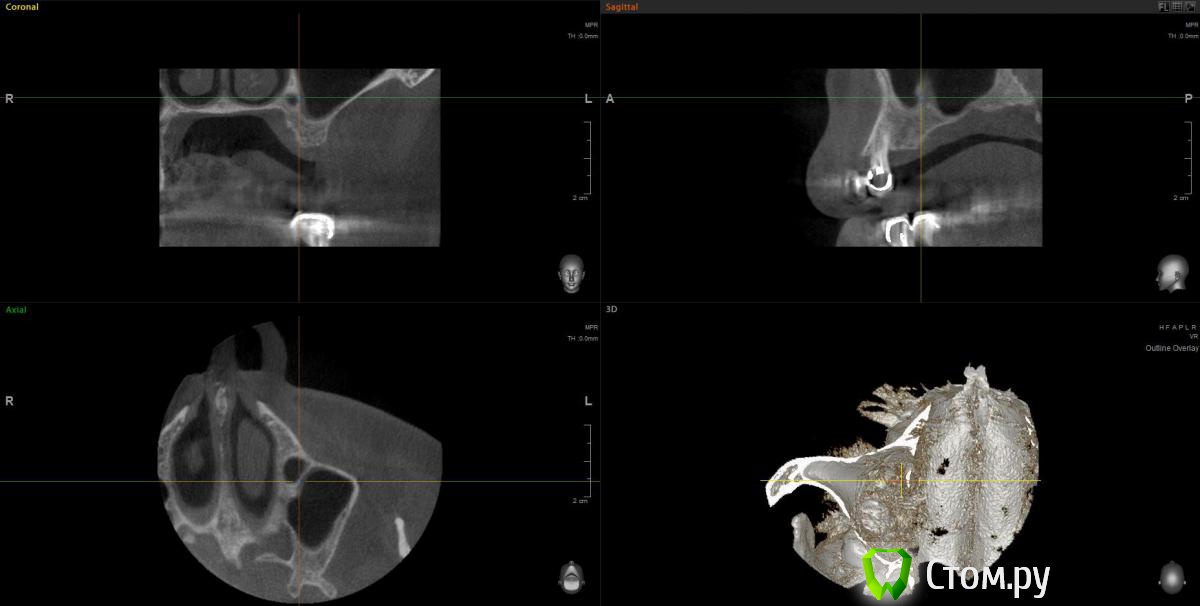

wladdX Опубликовано 11 февраля, 2014 Поделиться Опубликовано 11 февраля, 2014 (изменено) Прошу прощения за вторжение в чужую тему (администратор, поправьте), но ситуация похожа. Т.е. помимо синус-лифтинга надо увеличить ширину альвеолярного отростка. Предполагаю поступить примерно, как продемонстрировал Mane выше. Но может подойдёт "метод полужёстких каркасов? Кстати септа в пазухе замысловатая. По поводу остальных сегментов и прочих проблем - пациент на них не настроен, интересует его только зона 25,26,27 Изменено 11 февраля, 2014 пользователем wladdX Ссылка на комментарий

Sahan Опубликовано 11 февраля, 2014 Поделиться Опубликовано 11 февраля, 2014 Ну для планирования такой работы при КТ во рту должен был быть хирургический шаблон. А так никаких проблем. Открытый синус , плюс имплантаты , плюс сетка. Ссылка на комментарий

wladdX Опубликовано 12 февраля, 2014 Поделиться Опубликовано 12 февраля, 2014 Да, отсутствие шаблона при КТ, недочёт Хотя wax-up то сделан, недоработка, будем исправляться.По поводу сетки как-то не подумал даже, вероятно, потому что пока не пользовался. Возникает вопрос - для НКР под сеткой не слишком протяжённый дефект? Опасаюсь как-то в данной ситуации сразу имплантировать, первичной стабильности, скорее всего, не получить. Хотя сама по себе идея мне очень нравится: менее травматично и технически проще. Вот и чешу репу Ссылка на комментарий